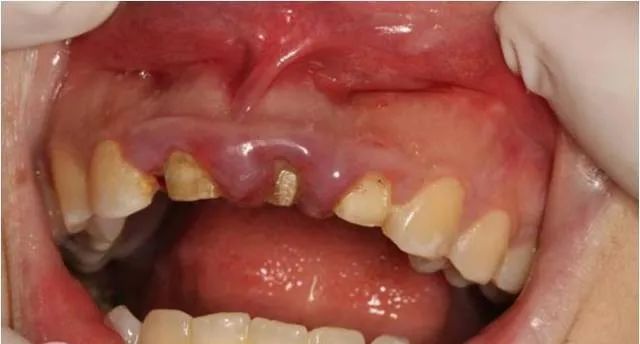

患者自述3年前上前牙因外伤折断在外院做烤瓷牙修复,现烤瓷修复体脱落。

经过检查发现,患者外露牙体组织不够,无法直接进行烤瓷牙重置。建议通过冠延长手术的方法,来使患牙的暴露量增加,然后再通过烤瓷牙进行牙齿的修复及改善牙龈形态的美观。与患者商议,表示接受该修复方案。

术前口内像